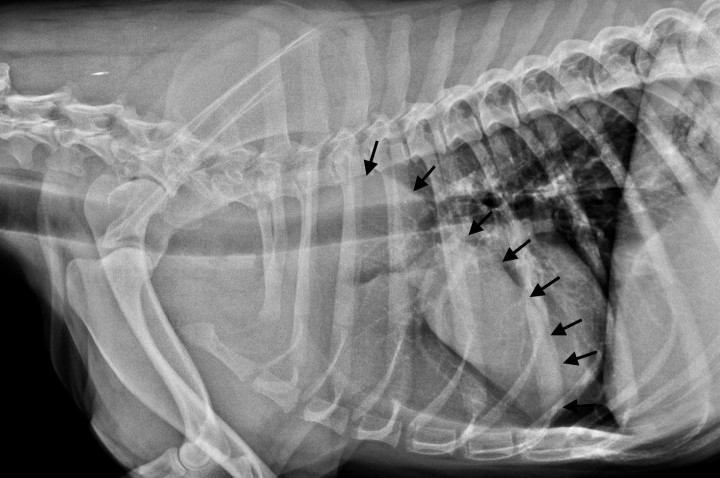

Una hembra mestiza de American bully, esterilizada de 2 años y 20 kg de peso fue remitida por un cuadro clínico de apatía, temblores, poliuria/polidipsia (PU/PD) e hiporexia de aproximadamente 3 semanas de evolución. Al examen físico, se auscultaron sonidos cardíacos disminuidos en el hemitórax craneal izquierdo. En el centro veterinario remisor se realizó una analítica sanguínea que mostraba valores elevados de creatinina (Crea), nitrógeno ureico (BUN) y calcio total (Ca). En el urianálisis obtenido mediante cistocentesis, se observó una gravedad específica de la orina (USG) de 1,015 y una ratio proteína creatinina (UPC) de 0,15 mg/dl (Tabla 1, día 1). La radiografía laterolateral derecha de tórax evidenció una estructura homogénea y ovalada con radiodensidad de tejido blando a nivel del mediastino craneoventral (Fig. 1).

Radiografía laterolateral derecha de tórax. En la región ventral del mediastino craneal se evidencia una opacidad ovalada con densidad de tejidos blandos, que se extiende cranealmente hasta la primera costilla y caudalmente hasta el sexto espacio intercostal, desplazando caudalmente el corazón. Dorsalmente, la lesión se extiende ventral a las 4 primeras vértebras torácicas (flechas negras).

Radiografía laterolateral derecha de tórax de control 15 días después de iniciado el tratamiento médico. En la región ventral del mediastino craneal se evidencia una opacidad ovalada de partes blandas, que se extiende cranealmente hasta la primera costilla y caudalmente hasta el 5 espacio intercostal. Nótese la considerable reducción de tamaño de la masa (flechas negras).